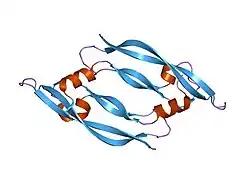

This gene is a member of the platelet-derived growth factor (PDGF)/vascular endothelial growth factor (VEGF) family and encodes a protein that is often found as a disulfide linked homodimer. This protein is a glycosylated mitogen that specifically acts on endothelial cells and has various effects, including mediating increased vascular permeability, inducing angiogenesis, vasculogenesis, and endothelial cell growth, promoting cell migration, and inhibiting apoptosis. Alternatively spliced transcript variants, encoding either freely secreted or cell-associated isoforms, have been characterized.[6]

Vascular endothelial growth factor A (VEGF-A) is a dimeric glycoprotein that plays a significant role in neurons and is considered to be the main, dominant inducer of the growth of blood vessels. VEGFA is essential for adults during organ remodeling and diseases that involve blood vessels, for example, in wound healing, tumor angiogenesis, diabetic retinopathy, and age-related macular degeneration. During early vertebrate development, vasculogenesis occurs which means that the endothelial condense into the blood vessels. The differentiation of endothelial cells is dependent upon the expression of VEGFA and if the expression is abolished then it can result in the death of the embryo. VEGFA is produced by a group of three major isoforms as a result of alternative splicing and if any three isoforms are produced (VEGFA120, VEGFA164, and VEGFA188) then this will not result in vessel defects and death of the full VEGFA knockout in mice. VEGFA is essential in the role of neurons because they too need vascular supply and abolishing the expression of VEGFA from neural progenitors will result in defects of the brain vascularization and neuronal apoptosis. Anti-VEGFA therapy can be used to treat patients with undesirable angiogenesis and vascular leakage in cancer and eye diseases but also could result in the inhibition of neurogenesis and neuroprotection. VEGFA could be used to treat patients with neurodegenerative and neuropathic conditions and also increase vascular permeability which will stop the blood-brain barrier and increase inflammatory cell infiltration.[7][8][9]